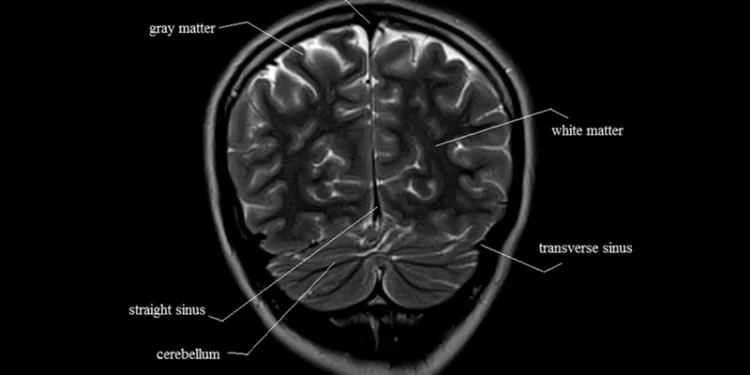

MRI brain anatomy helps doctors visualize the brain’s intricate structures with remarkable clarity. The main components of the brain that can be observed through MRI imaging include:

5. White and Gray Matter

- White matter consists of nerve fibers that transmit signals between different parts of the brain, while gray matter contains the neurons responsible for processing information.

- MRI can show the health of these tissues and identify changes that may signal conditions such as multiple sclerosis or stroke.